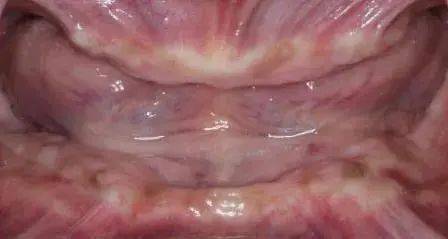

?种植牙前后口内照 , 左侧为戴牙前 , 右侧为戴牙后 。

文章图片